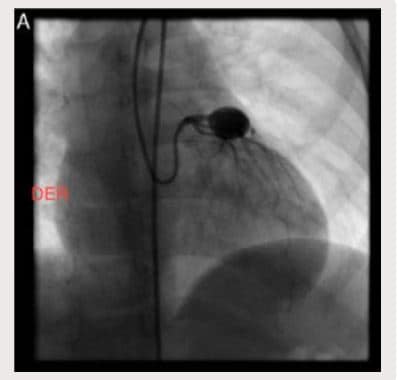

En control ecocardiográfico al mes aún persistían los aneurismas de igual tamaño. Dos meses luego del egreso, presentó fiebre de 39-40? durante dos días, consultó a Urgencias y se administró benzetacil por diagnóstico de amigdalitis. Se hospitalizó para estudio y presentó hipercolesterolemia, trombocitosis y pruebas de función hepática alteradas. El ecocardiograma evidenció aneurisma sacular gigante del tronco coronario izquierdo (13 mm) y dos aneurismas de tamaño moderado a grande (8,2 mm la proximal y 6,6 mm la distal) en la coronaria derecha (Fig. 1A y B). Se inició tratamiento con heparina durante dos meses y posteriormente se trató con warfarina 0,1 mg/kg/día y ácido acetil salicílico 50 mg/día. Se dio de alta con fórmula de ácido acetil-salicílico. Ante la persistencia de aneurismas gigantes se remitió para valoración por Hemodinámica, quienes ordenaron cateterismo cardiaco (Figs. 2A, 2B, 3A y 3B). Se trató con heparina de bajo peso molecular durante un mes y luego con Warfarina en forma permanente.

Figura 3 A. Cateterismo cardíaco en el que aprecia aneurisma gigante en la arteria coronaria izquierda.